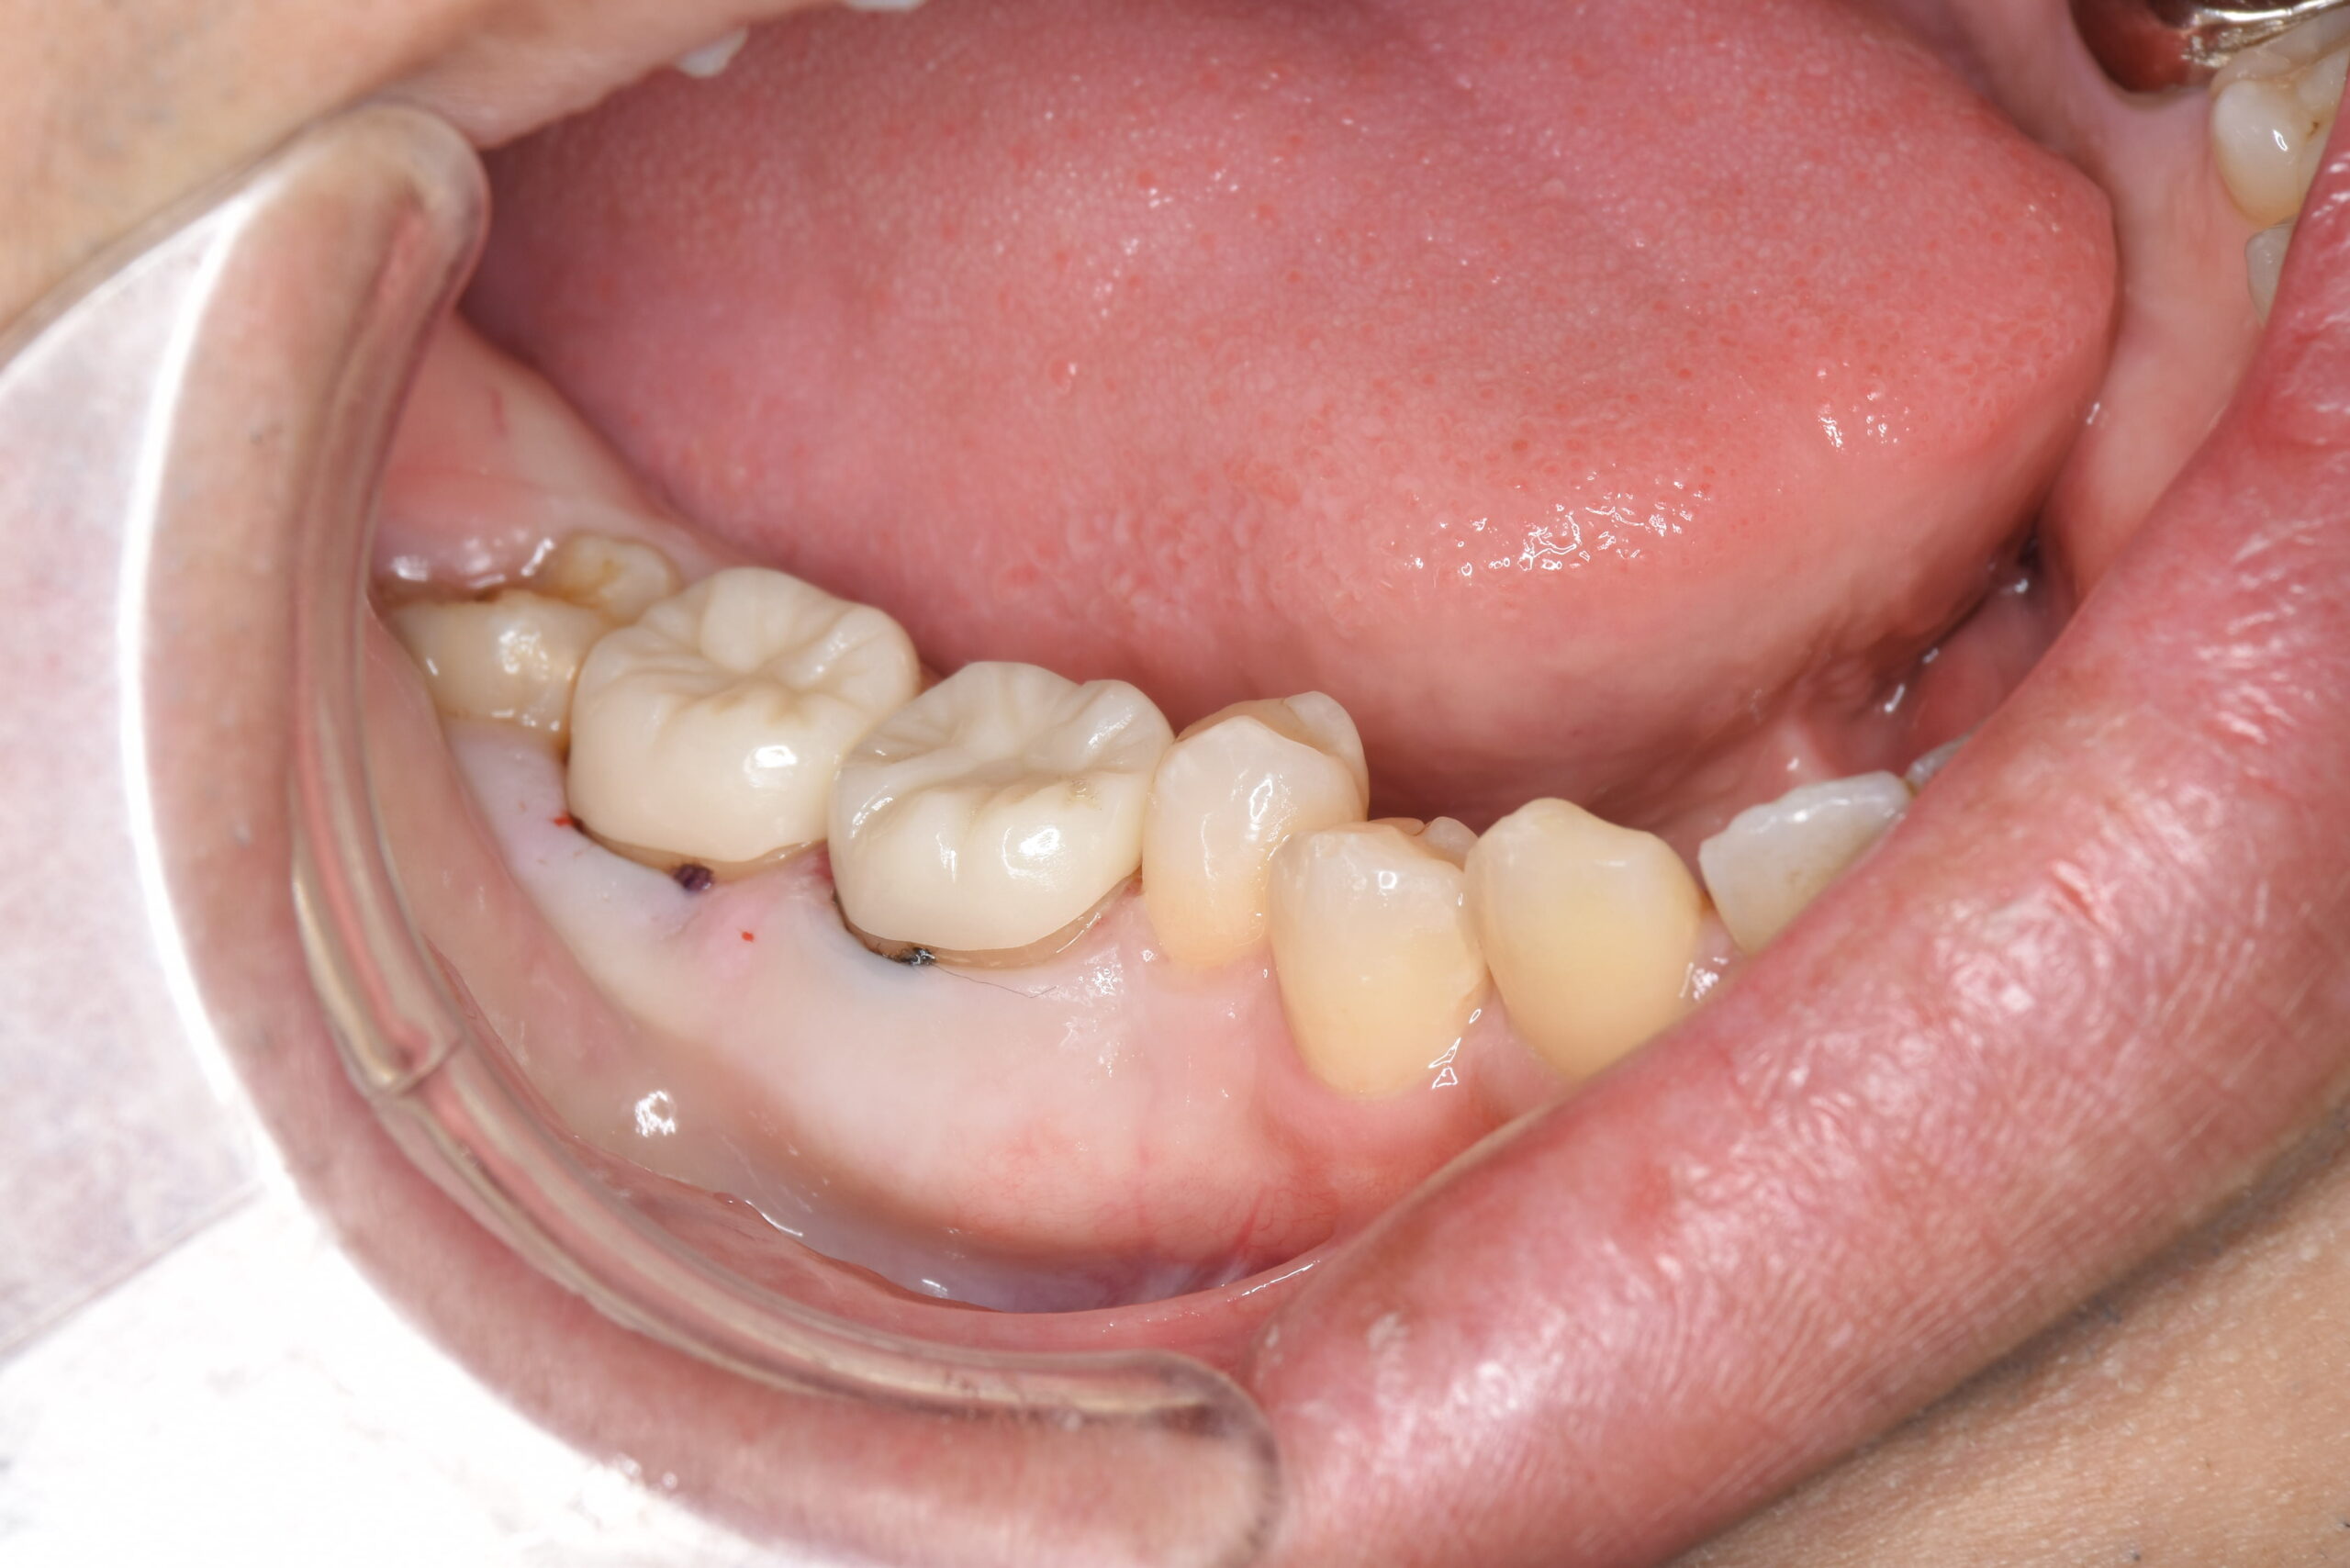

歯内療法専門医での根管治療終了後、当院にてセラミックによる被せ物治療を行いました。

現在は痛みもなく経過良好です。